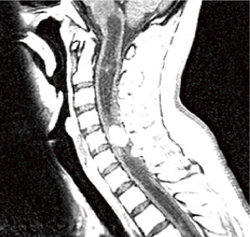

図6-1b 脊椎血管芽腫

脊髄空洞症様嚢胞を伴った脊髄血管芽腫。